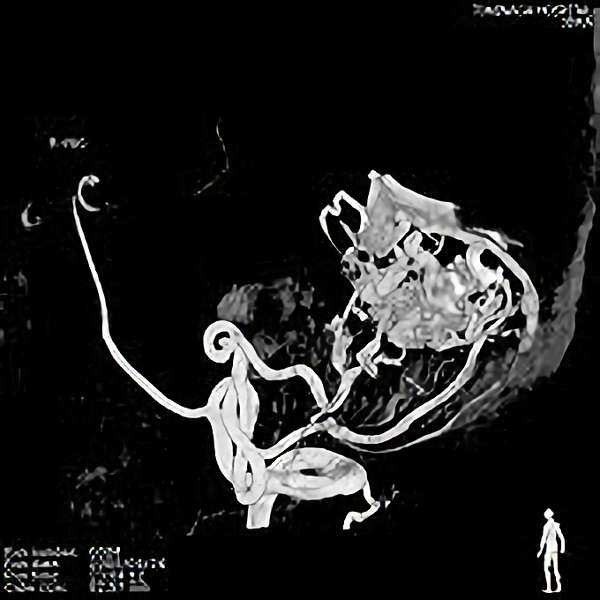

脳血管撮影

手術前

手術後